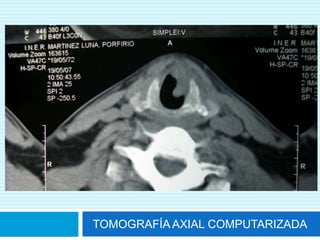

TOMOGRAFÍA AXIAL COMPUTARIZADA